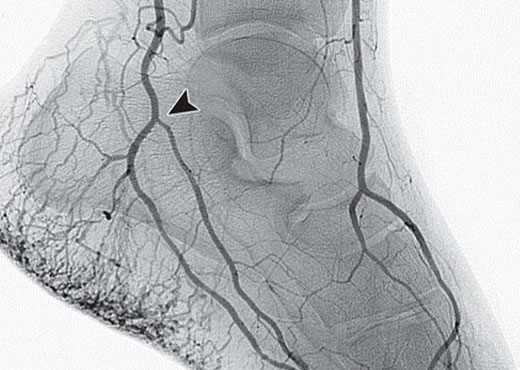

Procedimientos endovasculares

en los miembros inferiores y superiores

Este procedimiento se realiza para evitar posibles amputaciones en pacientes diabéticos. Se recurre a la angioplastía de miembros inferiores/superiores cuando hay dolor durante el reposo, hay gangrena o se presenta arteriosclerosis.